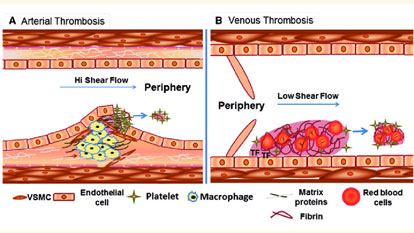

Intra-arterial & Venous Thrombolysis

Intra-arterial and venous thrombolysis is a minimally invasive procedure aimed at dissolving blood clots (thrombi) that obstruct...

Inferior Vena Cava (IVC) Filter Placement

Inferior Vena Cava (IVC) filter placement is a minimally invasive procedure used to prevent pulmonary...